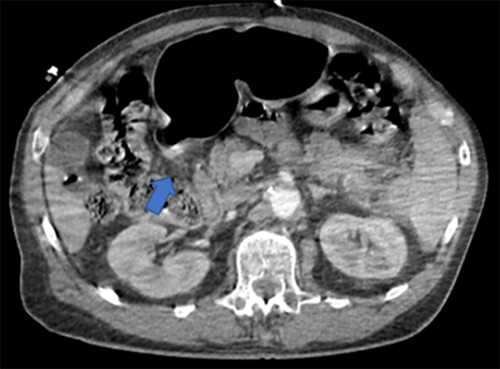

The patient underwent three orthopedic procedures for his extremity injuries on hospital days 1, 5, and 8, respectively. On hospital day 14, the patient became acutely tachypneic and hypoxic, requiring intubation and transfer to the intensive care unit. His hemodynamic lability required central line placement as well as intravenous fluid and vasopressor resuscitation. A CT chest and pulmonary embolism scan obtained earlier were negative for pulmonary embolism or other acute pulmonary processes. Due to concerns for sepsis of an unclear etiology, an abdomen and pelvis CT was obtained, and the patient was started on broad-spectrum antibiotics. The CT scan demonstrated stranding and free fluid centered in the right upper quadrant abutting the hepatic flexure and the second portion of the duodenum. There was poor visualization of a segment of the duodenal wall and a small volume of free air suspicious for duodenal perforation (Figure 2). His laboratory values were significant for an elevated white blood cell count of 22.7 Th/cmm with a left shift, lactate of 3.6 mmol/L, aspartate aminotransferase of 128 U/L, and alanine aminotransferase of 275 U/L.

Figure 2. Repeat CT Imaging of Abdomen and Pelvis Hospital Day 14 After Clinical Decompensation. Published with Permission

Imaging was suggestive of stranding and free fluid centered in right upper quadrant abutting the hepatic flexure and second portion of the duodenum. Note: poor visualization of duodenal wall segment and small volume of free air suspicious for duodenal perforation (arrows).